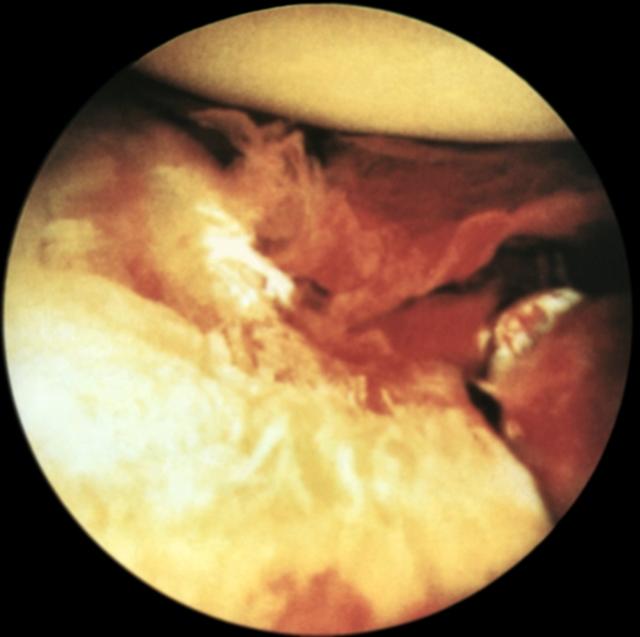

Рис. 20. Артроскопическая картина при полном свежем разрыве большеберцовой коллатеральной связки.